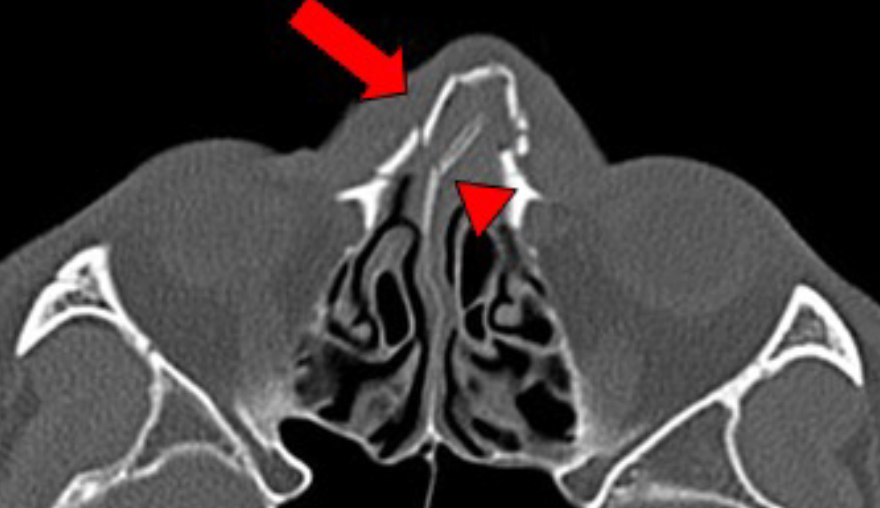

복합 골절 + 비중격 골절

비중격 골절이 동반될 경우 비중격 교정술을 동시에 시행하게 되며, 분쇄 골절이나 다른 안면 골절과 동반된 경우 정복 후 플레이트로 고정하거나 고정용 부목을 거치할 수 있습니다.

비중격 골절이 동반될 경우 비중격 교정술을 동시에 시행하게 되며, 분쇄 골절이나 다른 안면 골절과

동반된 경우 정복 후 플레이트로 고정하거나 고정용 부목을 거치할 수 있습니다.